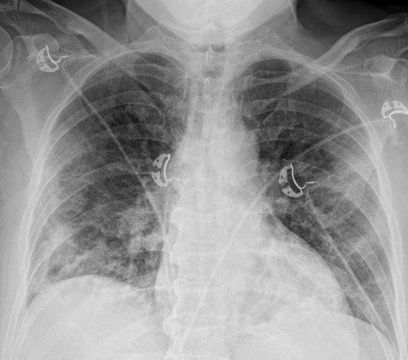

4.3. ЛУЧЕВАЯ ДИАГНОСТИКА COVID-19

Методы лучевой диагностики применяют для выявления COVID-19 пневмоний, их осложнений, дифференциальной диагностики с другими заболеваниями легких, а также для определения степени выраженности и динамики изменений, оценки эффективности проводимой терапии.

К методам лучевой диагностики патологии ОГК пациентов с предполагаемой/установленной COVID-19 пневмонией относят:

- Обзорную рентгенографию легких (РГ),

- Компьютерную томографию легких (КТ),

- Ультразвуковое исследование легких и плевральных полостей (УЗИ).

Стандартная РГ имеет низкую чувствительность в выявлении начальных изменений в первые дни заболевания и не может применяться для ранней диагностики. Информативность РГ повышается с увеличением длительности течения пневмонии. Рентгенография с использованием передвижных (палатных) аппаратов является основным методом лучевой диагностики патологии ОГК в отделениях реанимации и интенсивной терапии (ОРИТ). Применение передвижного (палатного) аппарата оправдано и для проведения обычных РГ исследований в рентгеновском кабинете. В стационарных условиях относительным преимуществом РГ в сравнении с КТ являются большая пропускная способность. Метод позволяет уверенно выявлять тяжелые формы пневмоний и отек легких различной природы, которые требуют госпитализации, в том числе направления в ОРИТ.